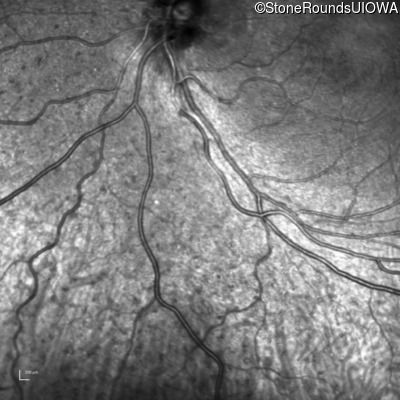

Infrared Fundus Photograph - Right - 20/25 -1

Exemplar